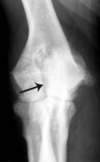

4-year-old Boerboel

White arrow - enthesophyte on the medial epicondyle Black arrow - dystrophic mineralization of the proximal flexor muscles Image - CC view showing the flexor muscle mineralisation